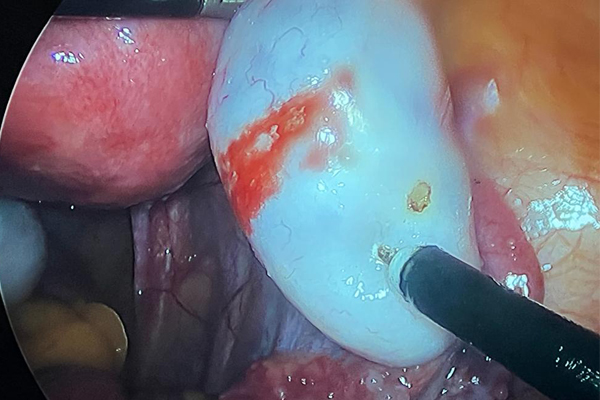

Dr. Mohankumar Veereshaiah has specialised in endoscopic surgeries in Gynaecology - (Laparoscopy and Hysteroscopy). He has an experience of 25 years. He has been giving excellent care to all his patients. His main location of practice is Navi Mumbai. He is attached to almost 30 hospitals in all over Navi Mumbai and all corporate hospitals like APOLLO, FORTIS, KOKILABEN, MGM Hospitals.

He has performed more than 15000/- surgeries to date. His vast experience in the field allows him to give top notch treatment to his patients. He has conducted many surgical conferences to teach his colleagues and students.